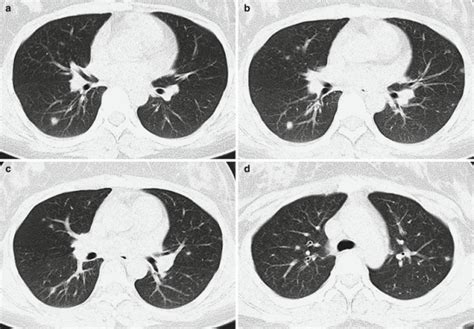

Alright, let’s kick things off by making sure we’re all on the same page about what Psittacosis actually is, because, let’s be real, that word itself is a bit of a tongue-twister, right? At its core, Psittacosis is a bacterial infection primarily found in birds, but – and this is the important part – it can totally jump to humans, which is why we’re giving it so much attention. It’s caused by a type of bacteria called Chlamydophila psittaci (don’t worry about remembering the full name, just know it’s a specific kind of bug!). This sneaky bacterium usually hangs out in various bird species, especially parrots, parakeets, cockatiels, and other types of psittacine birds (hence the name psittacosis !). But it’s not just limited to exotic birds; poultry like chickens and turkeys can carry it too, though it’s less common to see outbreaks in those specific populations. When birds get infected, they might not always show super obvious symptoms, which makes it a bit tricky. Some birds could seem totally fine, carrying the bacteria without showing a single sign of illness – these are what we call asymptomatic carriers . Other birds might get really sick, showing symptoms like ruffled feathers, lethargy, eye or nasal discharge, diarrhea, or difficulty breathing. This variability in symptoms is one of the reasons why keeping an eye on your birds’ health is so incredibly important, guys. The way humans usually catch psittacosis is through inhaling dust from dried bird droppings or respiratory secretions that contain the bacteria. It’s not typically spread through direct contact like petting a bird, but rather through the airborne particles. Think about cleaning a birdcage, being in an enclosed space with infected birds, or working in a poultry processing plant. These are situations where the risk of exposure goes up. Once a human is infected, the symptoms can range from a mild, flu-like illness to more severe pneumonia. We’re talking fever, chills, headache, muscle aches, and a dry cough. In rare but serious cases, it can affect other organs like the heart or brain, and if left untreated, it can even be fatal, though this is thankfully very uncommon with modern medical care. Early diagnosis and treatment with antibiotics are key to a full recovery, which is why awareness, especially for 2025, is so vital. Understanding these basics is our first step in being prepared and proactive. We’re aiming to empower bird owners, veterinary professionals, and really, anyone who interacts with birds, with the knowledge to recognize the potential risks and take appropriate preventative measures. It’s all about being informed and responsible , and this fundamental knowledge about psittacosis is the bedrock of that approach. So, while it sounds a bit intimidating, knowing the enemy is half the battle, right? And we’re here to help you win that battle, ensuring a healthier environment for both you and your beloved avian companions. It’s not about scaring anyone, but rather about equipping you with the facts so you can make smart, informed decisions. Let’s keep those feathery friends healthy and happy, while also safeguarding our own well-being.